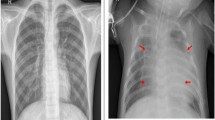

By training a CNN on a dataset of chest X-ray images, Deep Learning (DL)2,3,4,5 has been utilized to detect pneumonia6,7,8,9,10. As shown in Fig. 1, the CNN can learn to recognize patterns and associated features with pneumonia, such as clouded lung areas to detect pneumonia.The model can then be used to classify new X-ray images as normal or pneumonia. Multiple studies11,12,13,14 have demonstrated the efficacy of this method in detecting pneumonia with a high degree of accuracy. Attention mechanism isn DL refers15,16,17,18,19,20,21 to a technique used in neural networks to selectively focus on certain portions of an input as opposed to processing the entire input equally. In image detection and classification, attention mechanisms can be utilized to concentrate the network's attention on specific regions of an image that are most important for making a classification decision. This can help the network to improve its accuracy and decrease its computation needs. ViT models are a variant of the Transformer architecture22,23,24,25,26, which was originally designed for NLP applications. These models have been adapted for image classification tasks by handling an image as a sequence of image segments that are then processed by the transformer's attention mechanism. In addition, the ViT model outperformed state-of-the-art (SOTA) techniques on a broad variety of image classification tasks, making it an excellent candidate for the pneumonia diagnosis task.